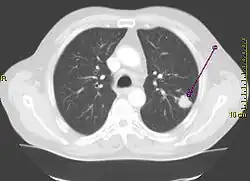

Der Unterschied zwischen der überlagerungsfreien Darstellung in der medizinischen Tomografie und einer Projektionsabbildung ist in den nachfolgenden Abbildungen illustriert. In Projektionsverfahren wie der Radiografie (gewöhnliche Röntgenuntersuchung) wird ein Schattenbild aufgenommen, auf dem sich mehrere Strukturen überlagern, wenn sie im Strahlengang hintereinander liegen. Beispielsweise überlagern beim konventionellen Röntgenbild die Weichteile der vorderen und hinteren Brustwand und die knöchernen Strukturen des Thorax die Lungenstrukturen. Dies würde die Diagnose eines Lungentumors (z. B. Bronchialkarzinom) erschweren. Jedes CT- oder MRT-Schnittbild vom Thorax zeigt dagegen nur eine 0,5 bis 10 mm dicke Schicht, die praktisch überlagerungsfrei ist.

Derselbe Tumor in der Computertomografie (axiales Schnittbild)

Derselbe Tumor in der Computertomografie (axiales Schnittbild) -